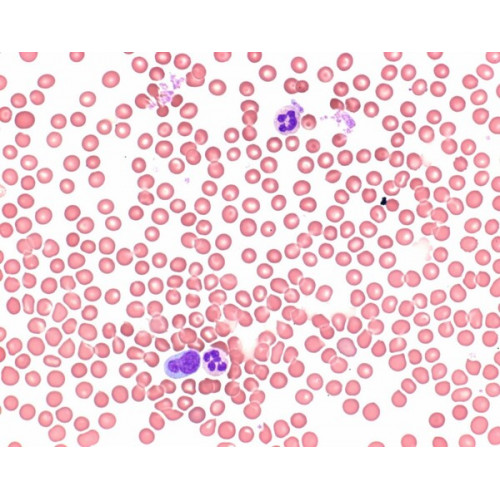

O método de coloração de acordo com Wright, é uma das técnicas padrão em procedimentos de diagnóstico hematológicas. Como solução de azul de metileno eosina de Leishman e solução de azul de metileno eosina de May-Grünwald, ele é usado para a coloração de sangue e medula óssea manchas e espécimes citológicos clínicos. Solução de azul de metileno eosina do Wright é um produto registrado IVD / CE e 500 ml são suficientes para a coloração até 1600 slides em células Hellendahl.